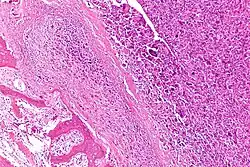

Intermediate-magnification micrograph of an osteosarcoma (center and right of image) adjacent to non-malignant bone (left-bottom of image): The top-right of the image has poorly differentiated tumor. Osteoid with a high density of malignant cells is seen between the non-malignant bone and poorly differentiated tumor (H&E stain).

Histopathology of osteosarcoma, showing tumor cells with high nuclear pleomorphism, but relatively less so in cells entrapped in neoplastic bone matrix (appearing pink on this H&E stained slide).